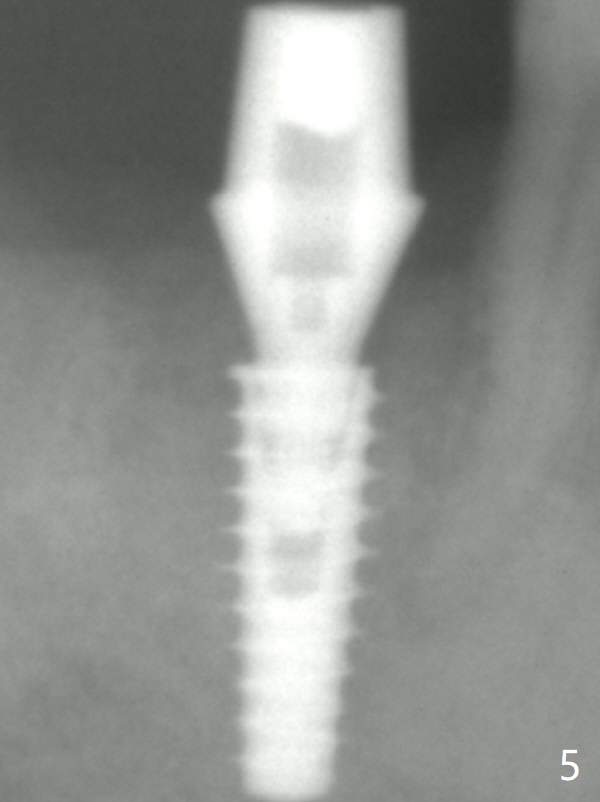

The definitive IBS implant (5x13 mm) is placed with 50 Ncm; a 6.5x5.7(4) mm abutment is placed with allograft filling the gap (* and arrow).

The final implant is placed a little too deep in this case.  The problem can be avoided by using Tap with soft tissue depth mark and is solved by using a longer implant (5x13 mm) or having an abutment with longer cuff (5 or 6 mm).  Postop there is tooth sensitivity.  When the latter disappears, the patient feels the right jaw different.  Panoramic X-ray taken 2 months postop shows that the implant has clearance from the Inferior Alveolar Canal (Fig.5 red dashed line).  The mesial margin is subgingival.  Laser gingivectomy is planned. Bone graft appears to remain in place.